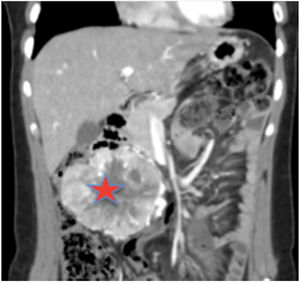

Se solicitó un estudio de localización mediante resonancia magnética nuclear (RMN) abdominal (figura 1 del anexo), que mostró una gran masa abdominal a nivel paraaórtico derecho compatible con un paraganglioma intraabdominal y estudio de extensión mediante tomografía computarizada (TC) toracoabdominal con contraste (figura 2 anexo) y gammagrafía con MIBG 131 (figura 3 anexo), que no mostraron lesiones a ningún otro nivel.

Una vez confirmado el diagnóstico, se inició tratamiento alfa-bloqueante con fenoxibenzamina a dosis progresivas (dosis final 10 mg/12 h) y a los cinco días se añadió tratamiento beta-bloqueante por taquicardia refleja (atenolol 25 mg/24 h). A los 20 días fue intervenida mediante laparotomía con extracción de masa extraadrenal derecha de 10 cm retroperitoneal (retrocava) y linfadenectomía peritumoral periaortocava e infrarrenal.